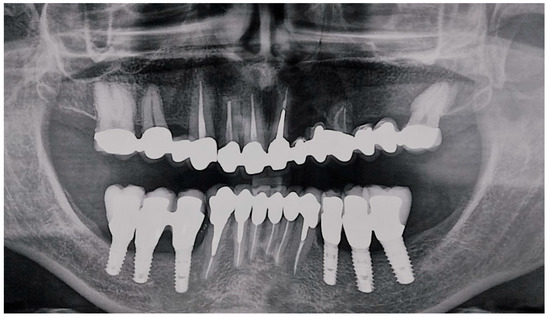

- Implant-supported prostheses from 3.4 to 3.6 and from 4.4 to 4.6.

- Prosthetic rehabilitation on dental support from 3.3 to 4.3. Metallic endocanalar posts in 3.3, 4.2, and 4.3.

- Endodontic treatment on 3.1, 3.2, 3.3, 4.1, 4.2, and 4.3.